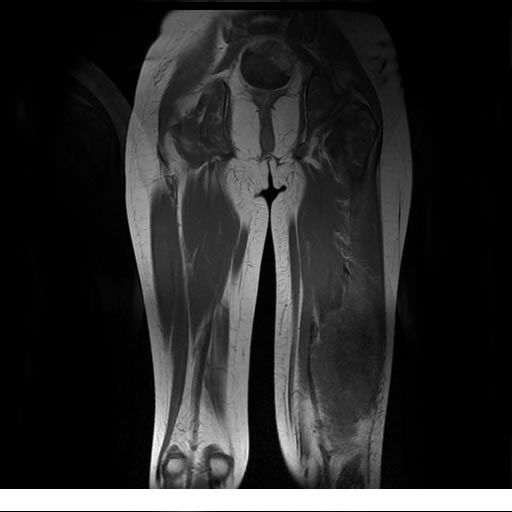

Se realiza estudio de MRI de muslo izquierdo en diferentes planos, con secuencias de Spin Echo, GRE; ponderadas a T1 y a T2, se utilizan pulsos de saturación de grasa y se administra medio de contraste IV a base de Gadolinio en base al peso del paciente.

La diáfisis femoral izquierda muestra reacción perióstica importante, se extiende desde el cuello del fémur, invade trocánteres, diáfisis femoral, medial y distal, es compatible con un proceso infeccioso óseo, el complejo muscular del muslo se ve edematizado.

La resonancia es la modalidad de elección para valorar la extensión intramedular y la infiltración en tejidos blandos, brindando una imagen más detallada del compromiso tumoral. Los hallazgos característicos incluyen:

Lesión de señal heterogénea en secuencias T1 (hipointensa) y T2/STIR (hiperintensa), que refleja necrosis, hemorragia y contenido celular diverso.

Realce intenso y heterogéneo tras la administración de contraste (gadolino), lo que indica vascularización tumoral.

Compromiso de la médula ósea adyacente y de estructuras vecinas, como músculos y neurovasculatura.

Posible presencia de edema óseo y necrosis central.